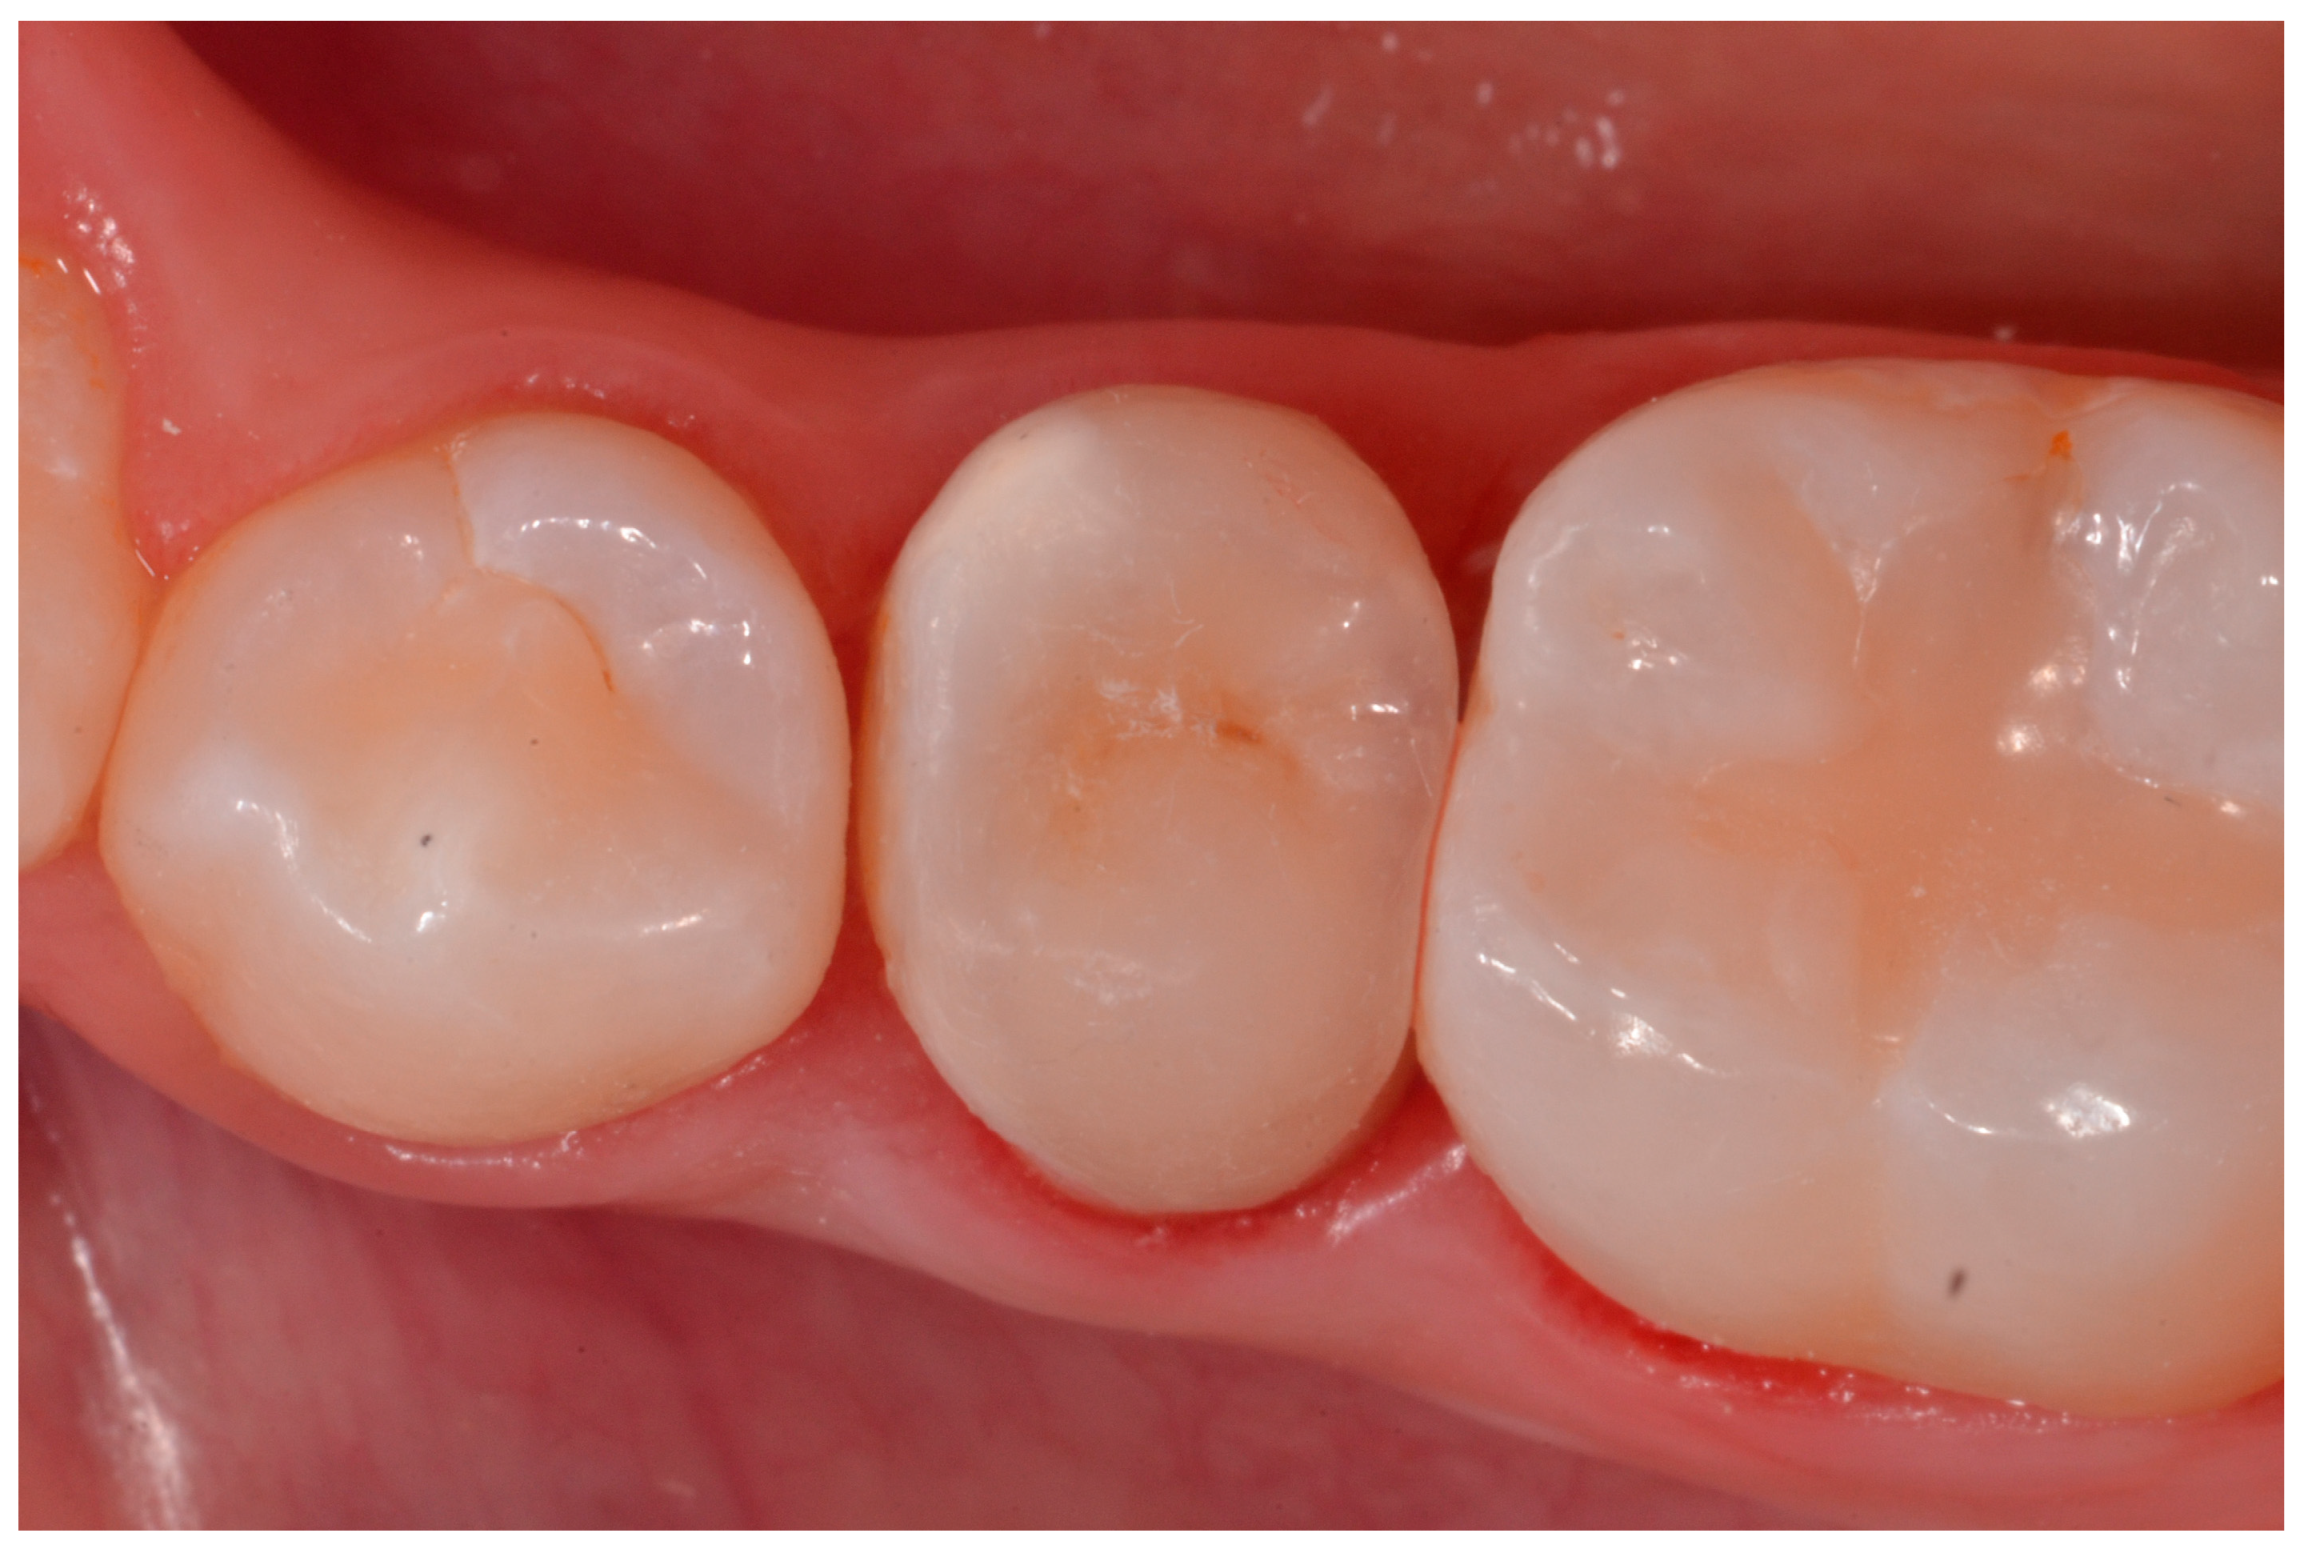

2.2. Case Presentation #1

2.2.1. Anamnesis, Physical Examination

2.2.2. Treatment